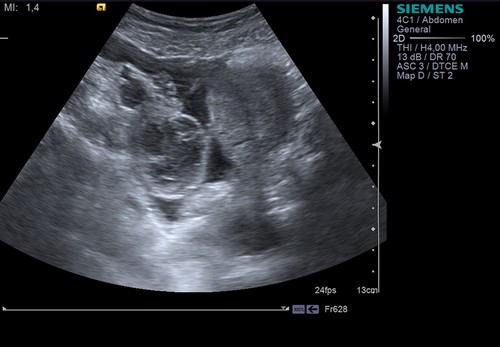

Исследование может быть выполнено как трансабдоминально, так и вагинально. В первом случае диагностика осуществляется аналогично стандартному УЗИ. Женщина располагается на спине, а живот обрабатывается специальным гелем, что способствует лучшему отображению изображения. Специалист перемещает датчик по животу от области грудины до лобка. На экране появляется изображение, после чего компьютер обрабатывает все полученные данные и предоставляет результаты. Второй метод, вагинальный, позволяет получить более детальную информацию. Датчик располагается ближе к яичникам, матке и эндометрию. Специальное устройство вводится во влагалище. Во время процедуры женщина может испытывать некоторый дискомфорт, однако в целом она безболезненна. Какой именно метод исследования будет использован, решает врач, который также устанавливает сроки проведения процедуры, так как время для фолликулометрии имеет свои ограничения.